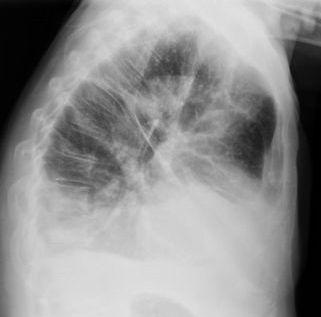

Fibrosis pulmonar. ICC.